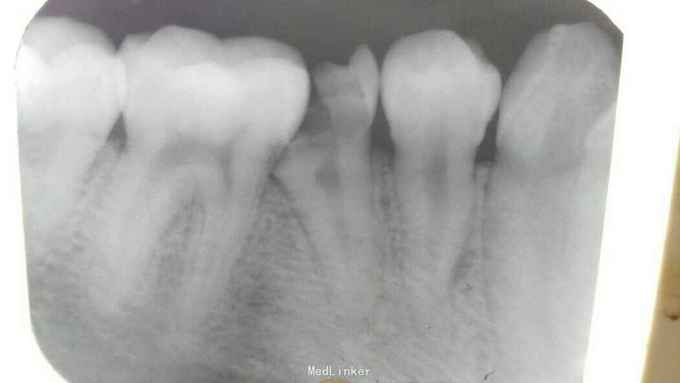

C4探诊-,叩诊+。C5探诊-,叩诊++ C5残冠,颊侧根部瘘管,触痛明显。 X线片显示,C5根尖阴影

C5慢性根尖周炎合并瘘管 C5去净腐质,开放根管,放置纸尖木溜油